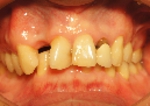

上顎全額的インプラント症例

上の全ての歯がぐらぐらな状態で左上の歯(写真向かって右上)が痛いとご来院。入れ歯は絶対に嫌ということで、まずは痛む左上(レントゲンでは右上)を抜歯、サイナスリフト(骨の移植)を併用しインプラント埋入して残りの歯で無理やり仮歯を支える。左上インプラントが生着し左で咬めるようになったら前歯(鼻の下がくぼんで老人様顔貌を避けるため骨の厚みを出す手術併用)、右上の歯はすべて抜歯して(ソケットリフト併用)しインプラント埋入。生着に時間のかかる日本承認の従来型のインプラントだったので計1年以上の治療期間を要しましたが一度もご自身の歯で咬めない時期はないようにしました。